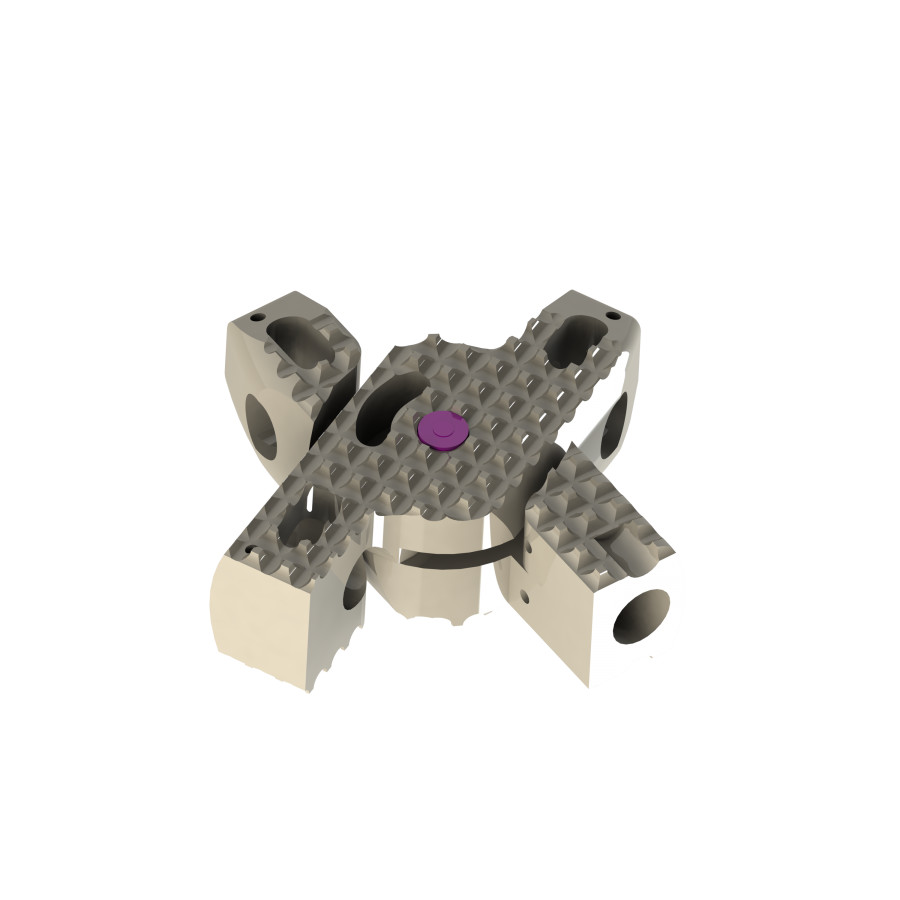

Aditus Lumbar Xlif Cage

- Anatomical Design

- PEEK Material and TI-6AL-4V ELI ( ISO 5832-3 )

- Titanium Alloy Material

- Titanium Pin Indicators for Radiological Imaging

- Special Thread Structure Providing Strong Adhesion at Surfaces of its Endplates

- Easy to Place within Disc Distance and Thanks to Elliptical Front Design

- Applicability of Posterior, Posterior Lateral or Extra Lateral from Disc Distance

- Functionality Leverage from 5 Points for Axial Loading Simple Implantation